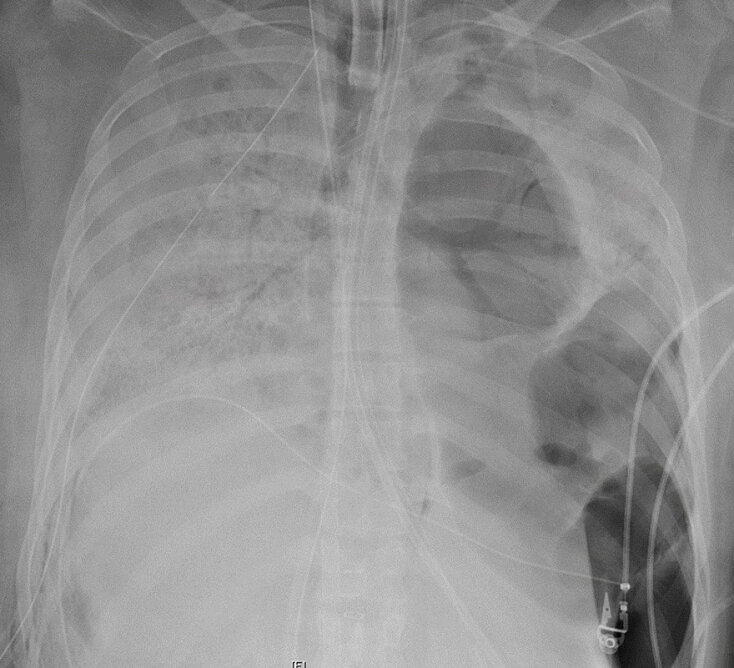

Μια 20χρονη, οι πνεύμονες της οποίας καταστράφηκαν «ανεπανόρθωτα» από τη νόσο Covid-19, υποβλήθηκε σε διπλή μεταμόσχευση πνευμόνων στο Σικάγο. «Η μεταμόσχευση πνευμόνων ήταν η μοναδική ευκαιρία της να επιβιώσει», δήλωσε η Έινκιτ Μπάρατ, η επικεφαλής της μονάδας θωρακοχειρουργικής στο νοσοκομείο Northwestern του Σικάγο, σε δελτίο Τύπου που εκδόθηκε μετά την επέμβαση.

Πρόκειται προφανώς για την πρώτη μεταμόσχευση αυτού του είδους στις ΗΠΑ, όχι όμως στον κόσμο, καθώς Κινέζοι γιατροί έκαναν διπλή μεταμόσχευση τον Μάρτιο.

Η ασθενής είναι μια ισπανόφωνη γυναίκα, που δεν αντιμετώπιζε κατά το παρελθόν προβλήματα υγείας, σύμφωνα με το νοσοκομείο, όμως νόσησε βαριά από τον νέο κορωνοϊό, σε βαθμό που χρειάστηκε να νοσηλευτεί 6 εβδομάδες στη μονάδα εντατικής θεραπείας.

«Για πολλές ημέρες, υπήρξε η πιο βαριά ασθενής στη μονάδα εντατικής θεραπείας Covid και πιθανόν σε ολόκληρο το νοσοκομείο», εξηγεί η Μπεθ Μάλσιν, πνευμονολόγος στο Northwestern. Ωστόσο, χρειάστηκε να περιμένουν για να γίνει η μεταμόσχευση, προκειμένου η ασθενής να βγει αρνητική στον κορωνοϊό.